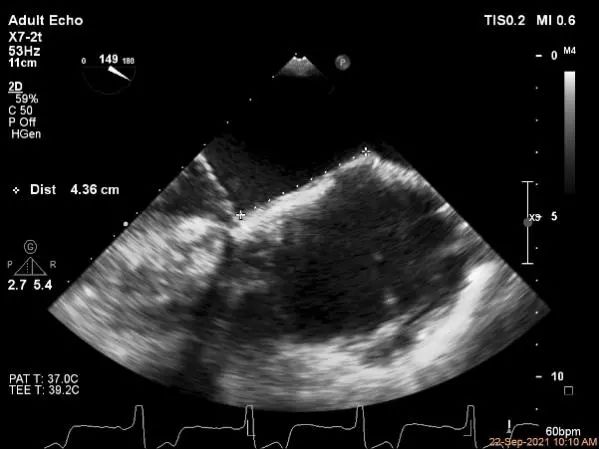

房间隔穿刺点选择

穿刺高度:4.3cm